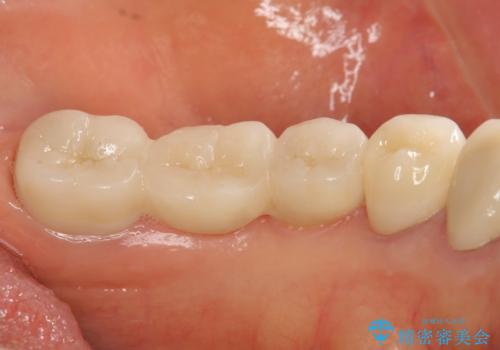

清掃しづらく、見た目の気になるブリッジ

- 毎回食事のたびに食べかすがつまり、見た目も気になる銀歯のブリッジやりかえを希望され来院されました。

精度の高いジルコニアブリッジの製作に加え歯茎にぴったりとそわせたオベイトポンティック形態とすることで清掃性・審美性に優れたブリッジを製作します。

- 35万円(仮歯・ファイバーコア・ジルコニアクラウン×3)費用は治療当時の料金となります

歯ぐきの形態にそわせ、凸型でくぼみのないオベイト型のポンティックはプラークの溜まりにくく審美性も達成できるポンティック形態です。